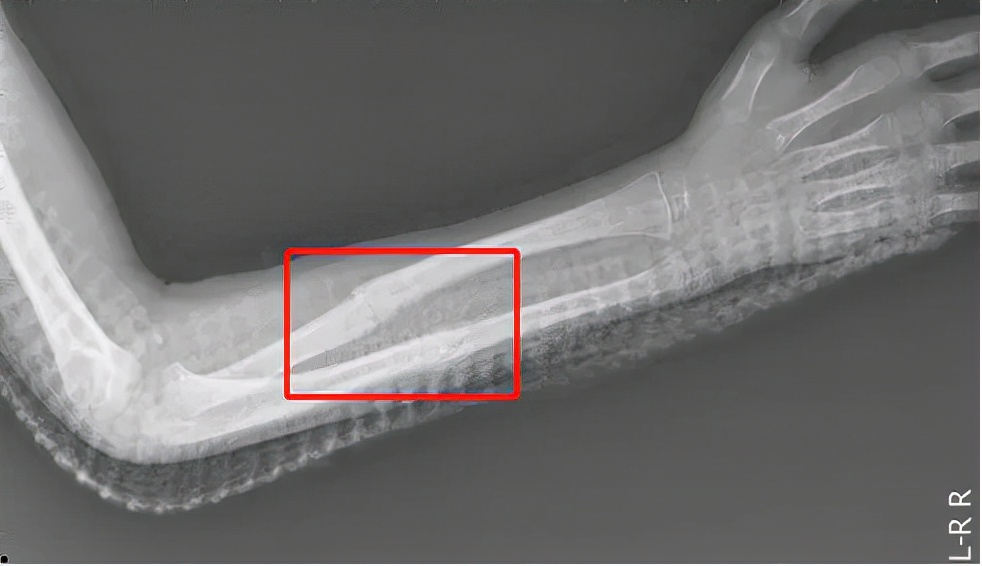

骨质疏松主要表现为骨小梁骨微结构被破坏,骨内部的“钢筋”消失了,骨骼硬度自然会降低,就容易产生骨折。所以,患了骨质疏松的患者可能会因稍微一点碰撞或能量转移,如“平地摔”、“上下楼摔倒”、“扭伤”等因素出现骨折。